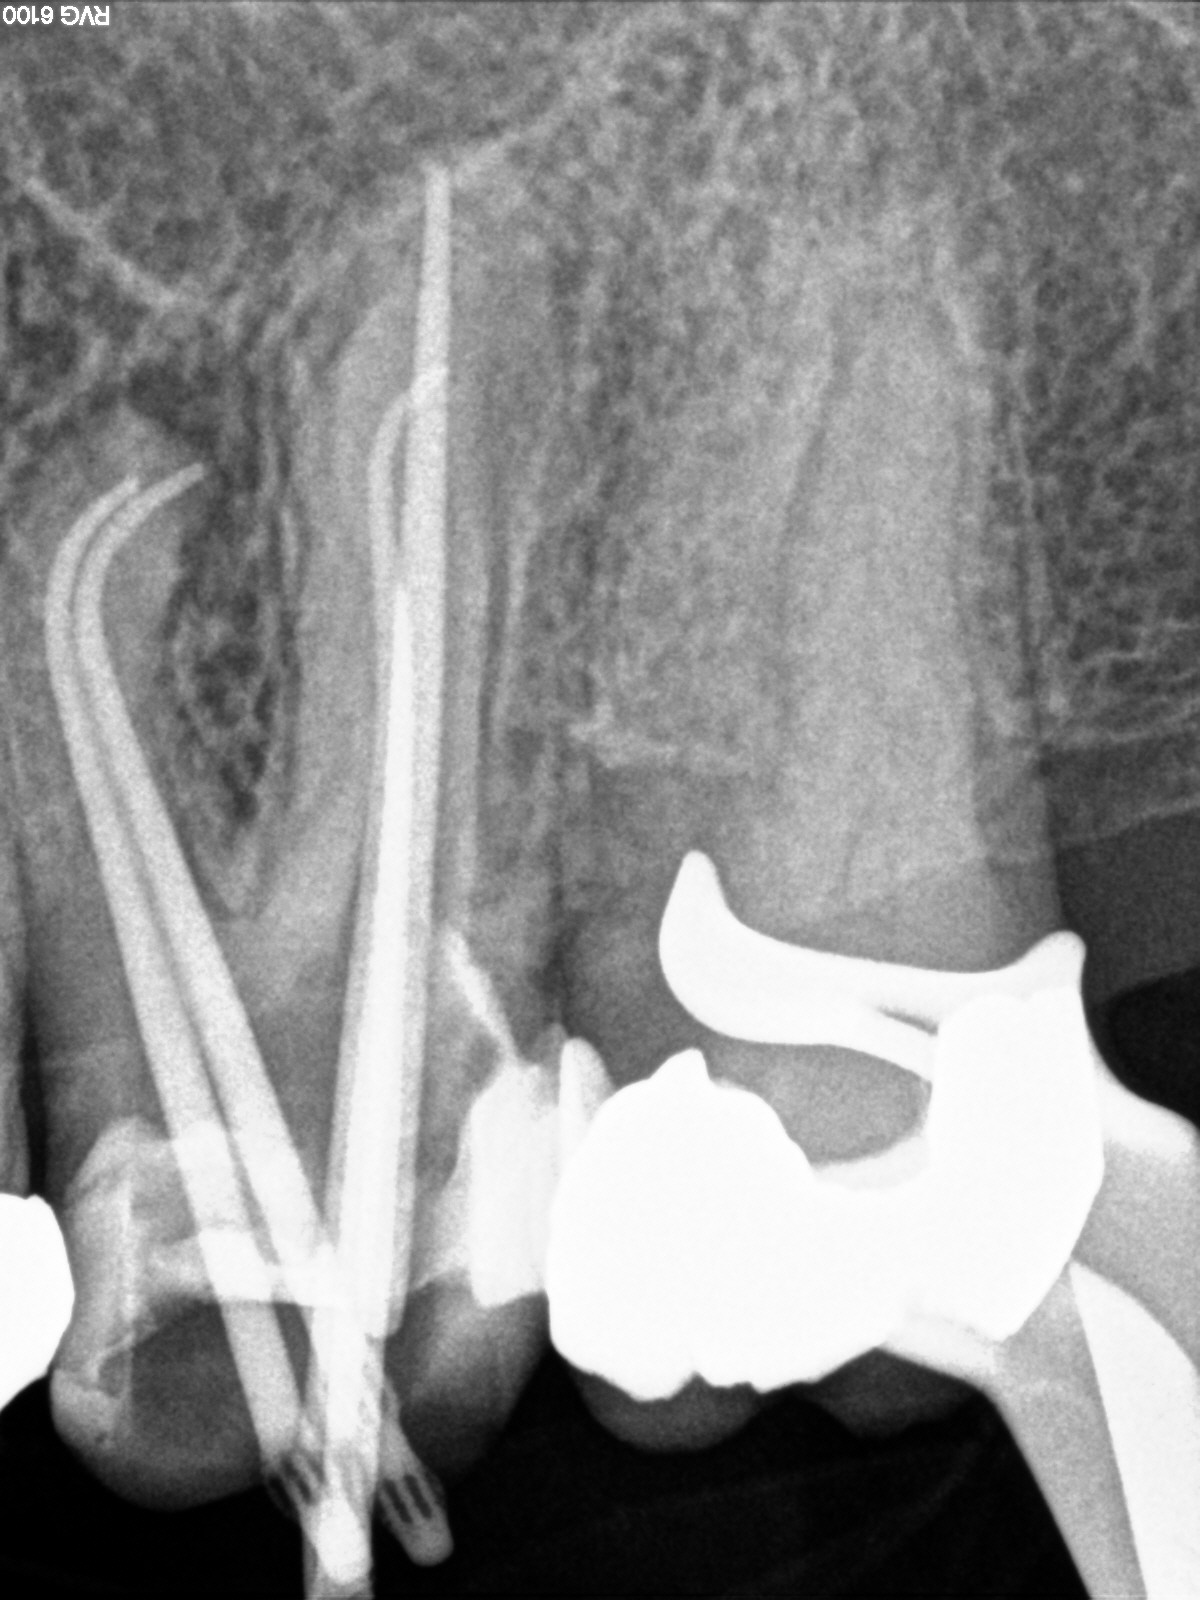

Deutliche Krümmung und kein DVT!